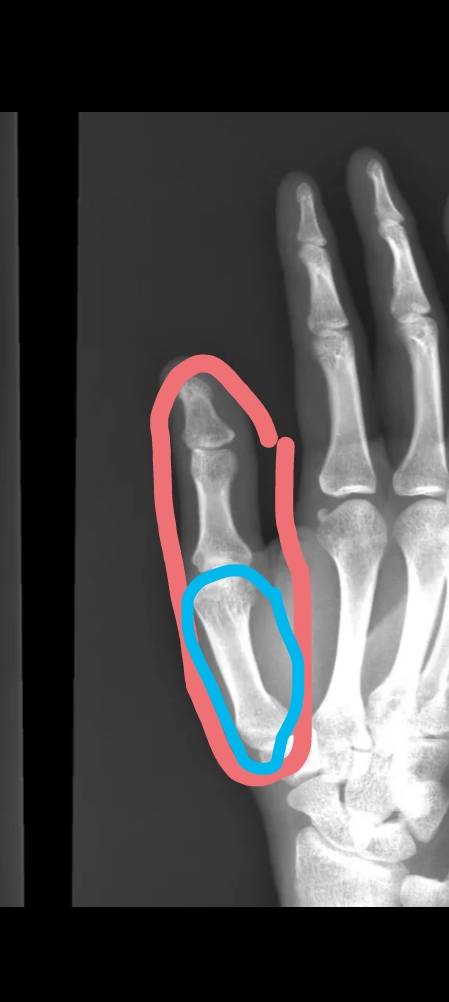

Онемение правой руки уже с 13 числа. Спала неудобно, что большой палец на ноге подвернут был, в итоге отлежала его, проснулась и рука в этом месте,чтотна фото, онемела. Сегодня ещё и нога в щикололке чувствуется какой-то не такой. Ничего не болит, все вращается, кулак сильно сжать могу. Что со мной? Шея? Мозг? Спина? У кого так было? (((((